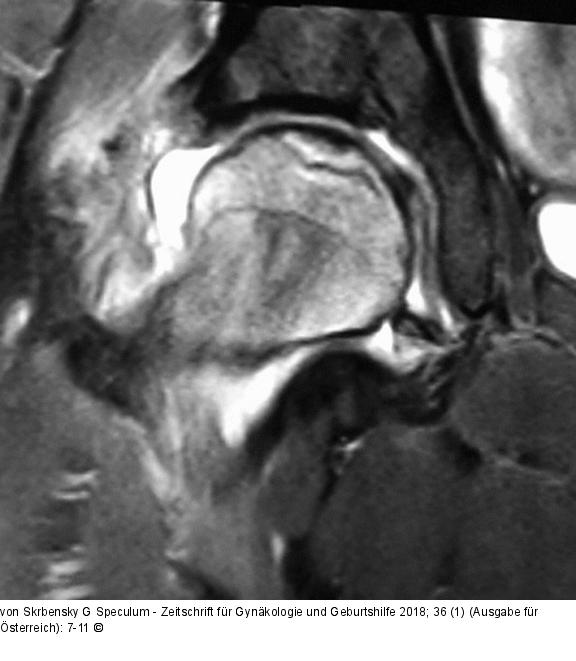

Abbildung 4: ARCO IIIa

Prä-OP: Pat. 36a, ARCO IIIa